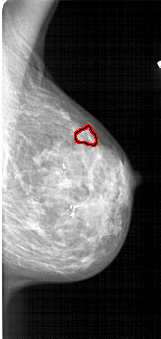

FILE: A_1713_1.RIGHT_CC.OVERLAY

TOTAL_ABNORMALITIES 1

ABNORMALITY 1

LESION_TYPE CALCIFICATION TYPE PLEOMORPHIC DISTRIBUTION CLUSTERED

ASSESSMENT 4

SUBTLETY 1

PATHOLOGY BENIGN

TOTAL_OUTLINES 1

BOUNDARY